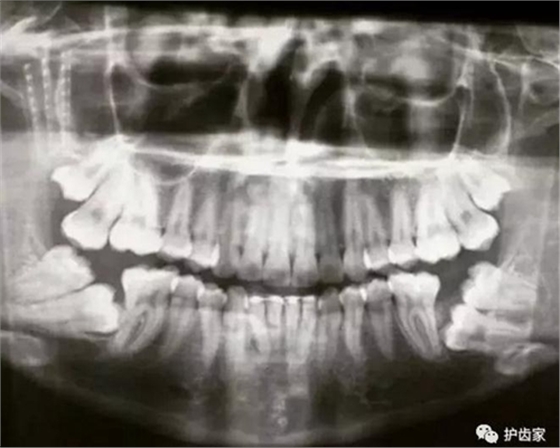

拍片是為了了解智齒周圍情況,也是為了了解智齒結(jié)構(gòu),牙根結(jié)構(gòu)千變?nèi)f化,有可能是融合成一個(gè)根,也可能是八爪根。不同牙根不同位置及方向,只有通過拍片來確認(rèn)。

拍片也為了了解下頜神經(jīng)與智齒的關(guān)系,一般離得近,有醫(yī)療風(fēng)險(xiǎn)的,基本沒有醫(yī)生愿意拔,現(xiàn)在沒人為了幾百元,賠上自己的職業(yè)生涯。誰都怕拔智齒,敲打智齒,一不小心,碰到神經(jīng),就攤上大事了。有理都說不清。

通過拍片可以了解牙齒本身:生長方向,牙根數(shù)目,牙根是否彎曲,膨大等。

與重要解剖結(jié)構(gòu)的位置關(guān)系:如上頜磨牙與上頜竇的關(guān)系;下頜磨牙與下頜神經(jīng)管的關(guān)系;兒童在混合牙列期恒牙與乳牙胚的關(guān)系等??梢詼p少拔牙的風(fēng)險(xiǎn)。

預(yù)知其他病變:如頜骨內(nèi)有無埋伏牙,多生牙,囊腫等。